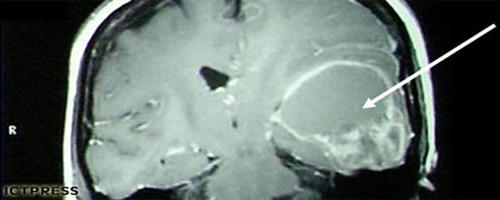

استفاده از ذرات نانو برای نشان دار کردن سلولهای تومور

ICTPRESS - محققان به تازگی موفق به اراده روشی شده اند که در آن از نانوذرات برای نشان دار کردن سلولهای تومور استفاده می شود .این امر موجب می شود که جراحان راحت تر بتوانند این سلولها را شناسایی کرده و از بین ببرند .